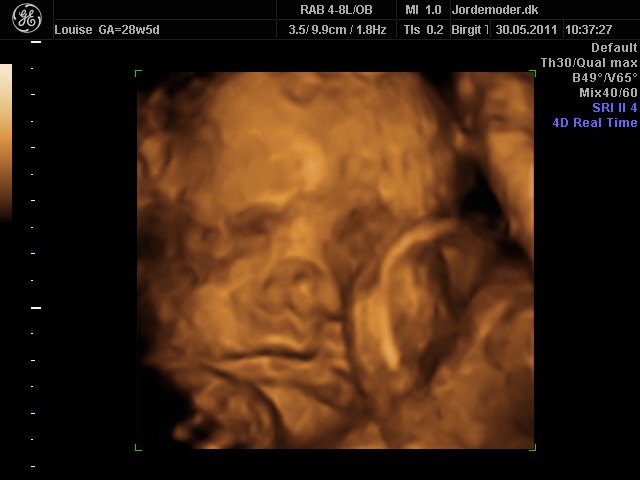

Moar2011

i uge 28

Vedhæftede fotos (klik for at se i fuld størrelse)